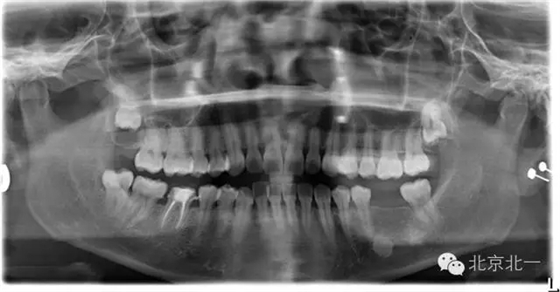

先看一例病例。頜骨內(nèi)單發(fā)高密度影像。是什么?能不能影響種植, 骨島是什么鬼?需要怎么處理?

如已經(jīng)證實(shí)骨島,是可以進(jìn)行種植牙。但是骨島和致密性骨炎不好區(qū)別。 因?yàn)橹旅苄怨茄兹绻M(jìn)行種植必將失敗,切記!切記!切記!

總結(jié):出絕招,如果遇到診斷不明確的骨島或者高密度影像, 最好的方式就是躲避, 不碰及它。

【口腔種植】致密性骨炎/牙骨質(zhì)增生/骨島如何鑒別?

頜骨三種高密度影像的鑒別

1)致密性骨炎

概述:

是指根尖周組織受到輕微緩慢持續(xù)性的低毒性因素刺激,而表現(xiàn)出以骨質(zhì)增生為主的防御性反應(yīng)。一般無(wú)自覺(jué)癥狀,多見(jiàn)于青年人,下頜第一磨牙多見(jiàn),常有較大齲壞。

【CBCT表現(xiàn)】:發(fā)生致命性骨炎的環(huán)亞暢游牙體病變,其CBCT表現(xiàn)為圍繞根尖的骨質(zhì)密度增高區(qū),骨小梁增多增粗,骨髓腔變窄甚至消失,與正常骨組織分界不明顯。根尖部牙周膜間隙可增寬,根尖無(wú)增粗膨大。

根尖片顯示D6深齲,根尖低密度區(qū)周圍骨小梁增粗、增多,骨質(zhì)密度增高,骨髓腔變小(黑色箭頭)。

3)骨島:

主要和根尖型骨島鑒別,主要集中位于根尖區(qū)的骨島,

【CBCT表現(xiàn)】:

在CBCT上,根尖型骨島無(wú)低密度帶狀影包繞,與周圍骨質(zhì)分界清晰,具有特征性的毛刷樣邊緣,且其發(fā)生區(qū)域的牙根牙周膜影像連續(xù)、完整、不導(dǎo)致頜骨的膨隆。

右下頜C4根尖區(qū)課件一類圓形高密度影,與周圍骨質(zhì)分界清晰,C4牙周膜影像連續(xù)、完整,下頜骨未見(jiàn)膨隆。